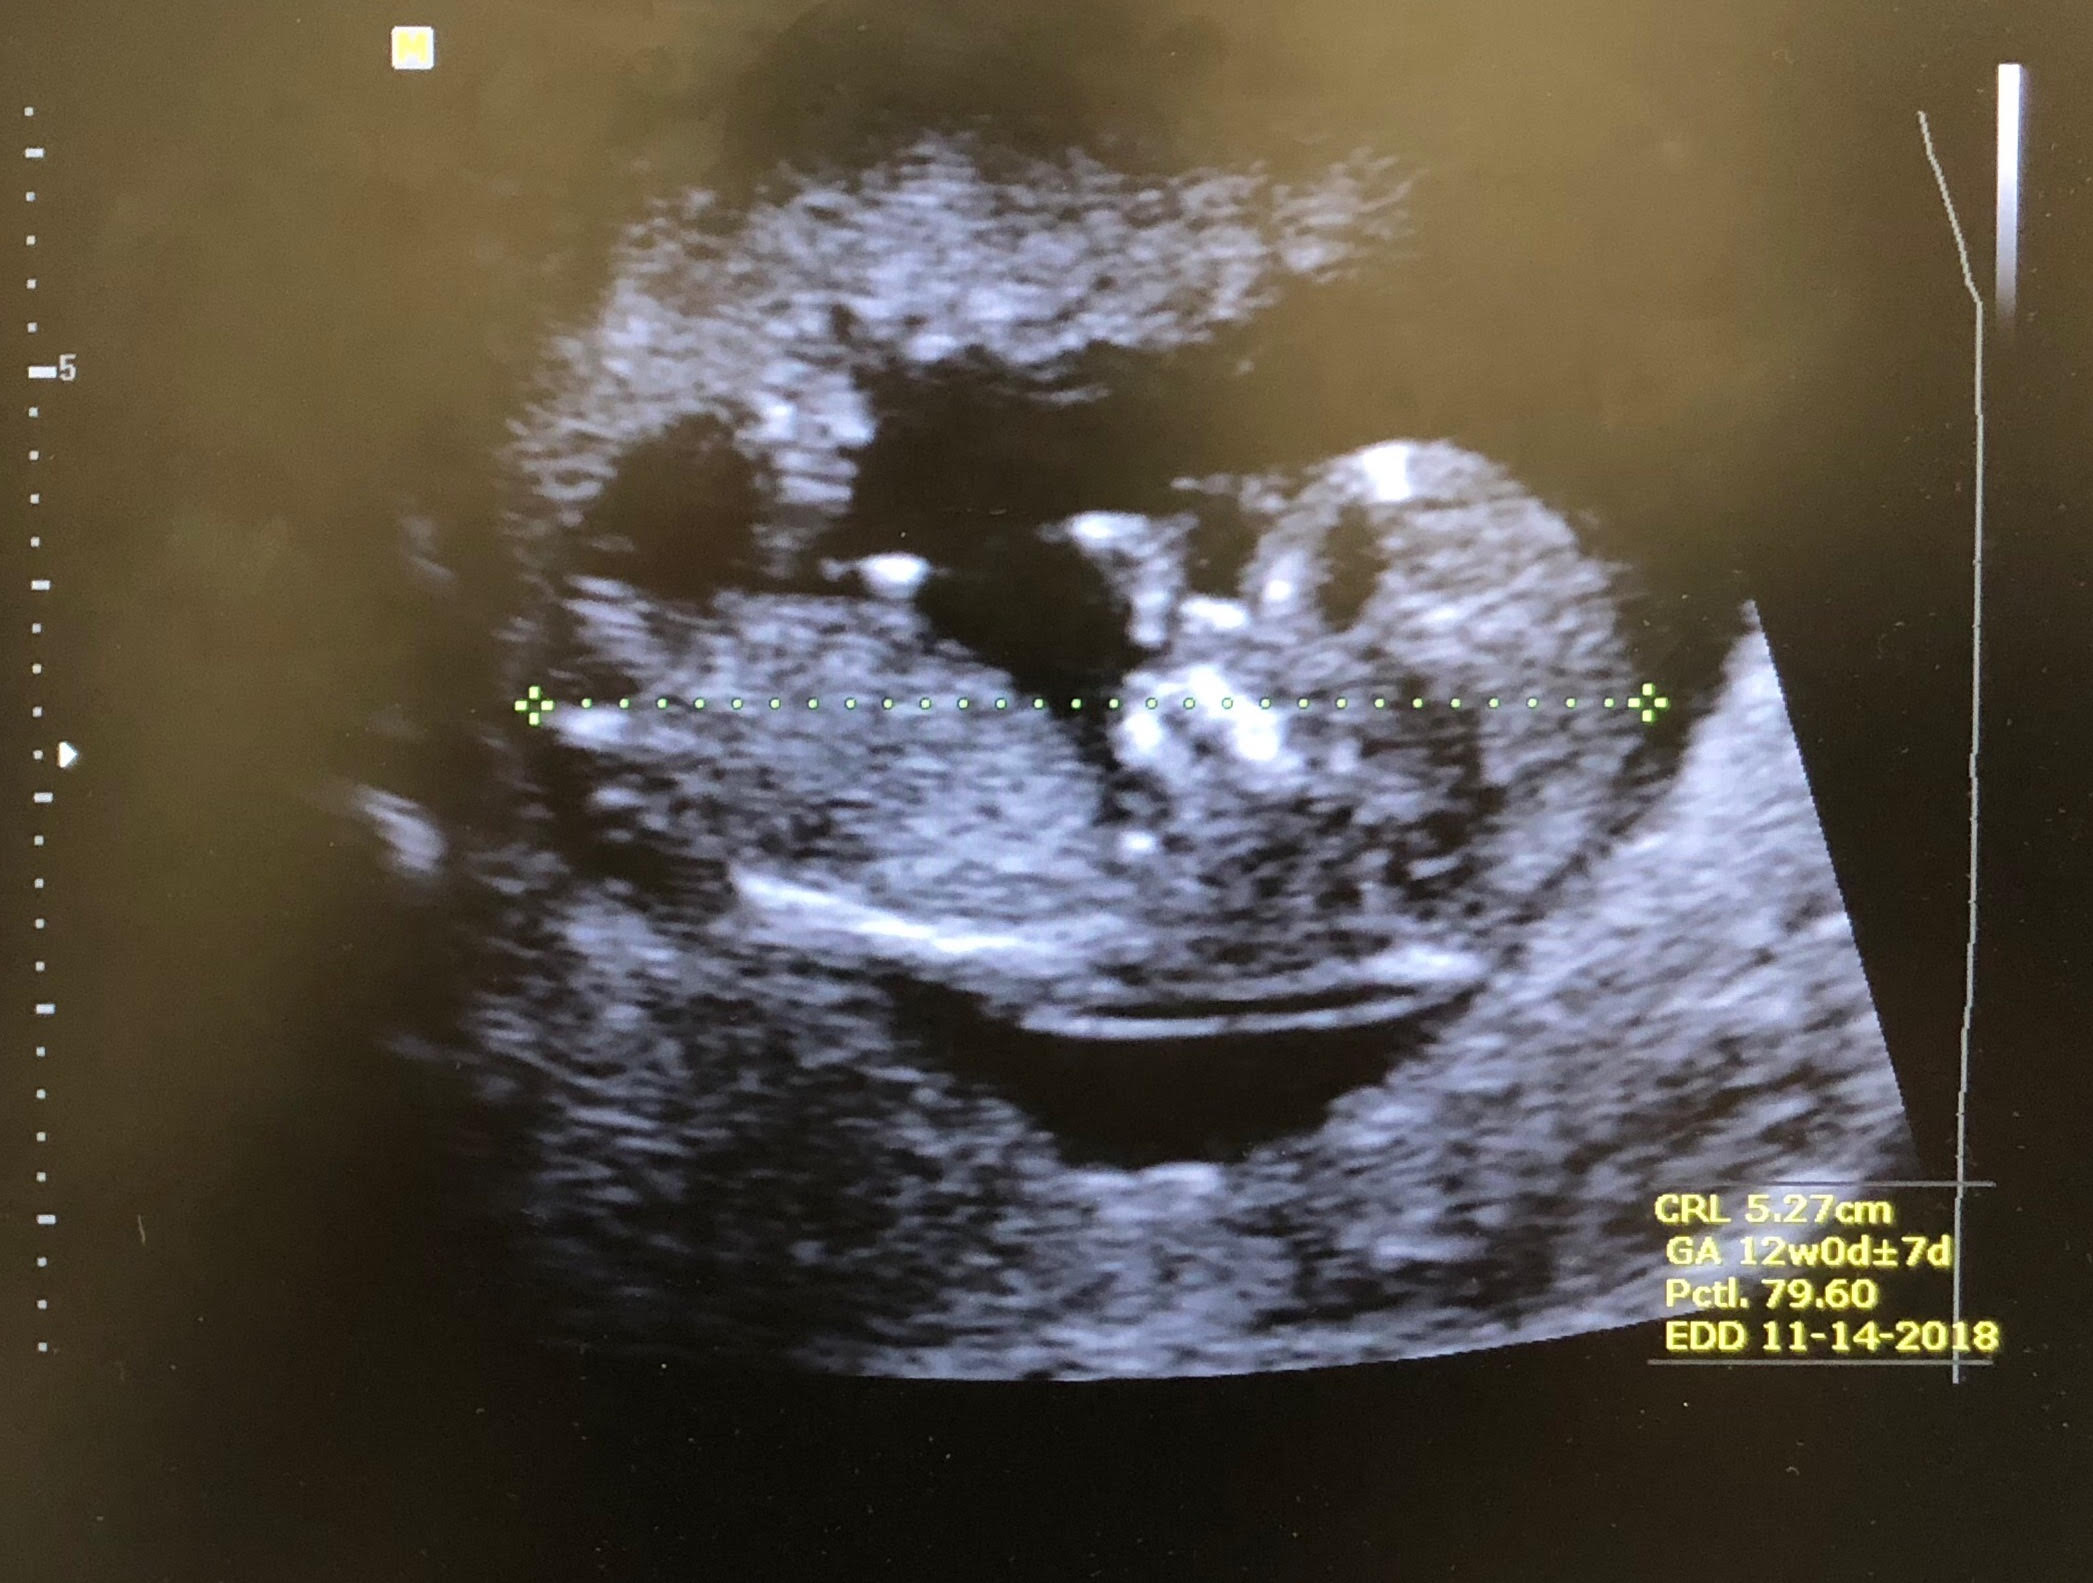

Hello! 12-week scan of the little one here. Any predictions?

Right at 12 weeks is a bit early for nub guesses. The nub really isn't very clear anyway, sorry.